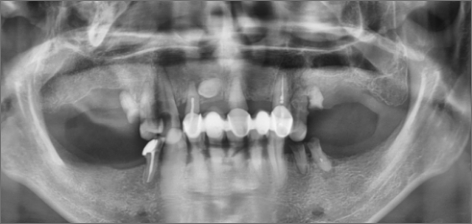

치료 후 : 2015.11.17

치료 기간 : 2014.01.18 ~ 2024.02.03

THE 이해승치과에서 2014년 치료 받으신 40대 환자분의 사례입니다. 흡연과 음주가 근본 원인이 되어 2014년 전악 임플란트 치료를 받으셨습니다. 감사하게도 저희와 함께 꾸준히 10년 관리를 동행해오시면서 추가적인 전신 질환 없이 건강한 50대를 보내고 계십니다. 치료 경험을 통해 변화를 만드신 환자분을 존경합니다.